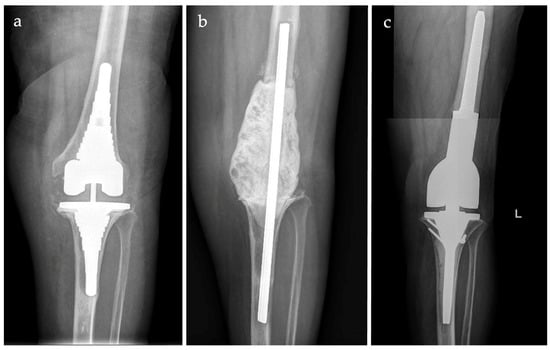

Silver-Coated Distal Femur Megaprosthesis in Chronic Infections with Severe Bone Loss: A Multicentre Case Series

3. Results